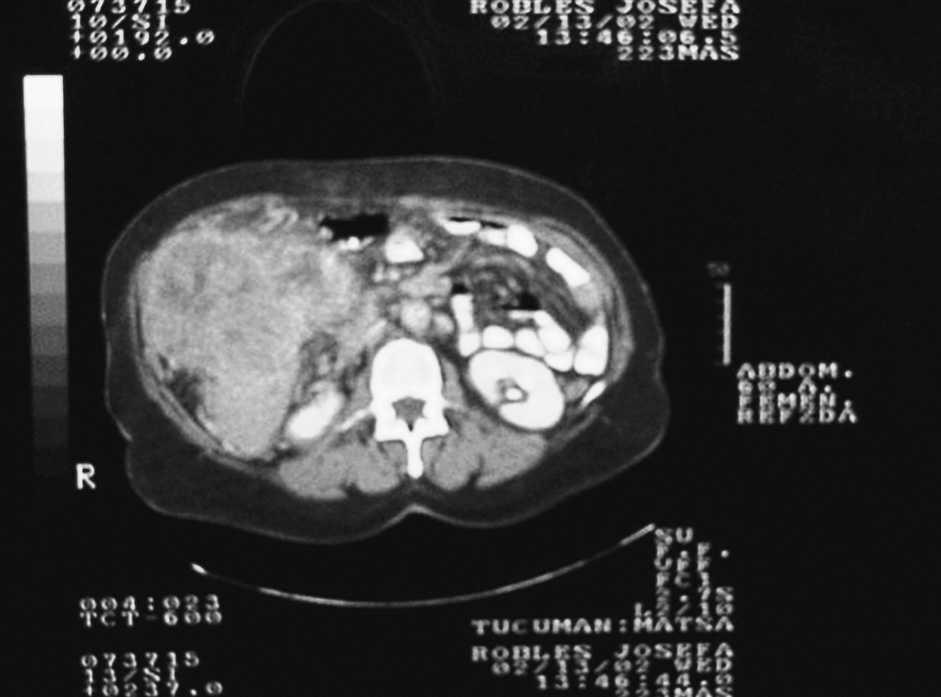

Caso 1. Paciente de sexo masculino de 76 años que consultó por disnea y dolor costal derecho. En una radiografía se detectó derrame en hemitórax homolateral y el drenaje confirmó hemotórax. Una tomografía computarizada mostró en los cortes inferiores una formación nodular en hígado. La resonancia magnética confirmó nódulo de 3 cm en segmento 7 con efracción capsular (fig. 1). El paciente no aceptó tratamiento y falleció a los 2 meses, con insuficiencia hepática.

Fig. 1. Paciente de sexo masculino, de 76 años, con cirrosis alcohólica. Tumor de 3 cm, segmento 7, efracción capsular.